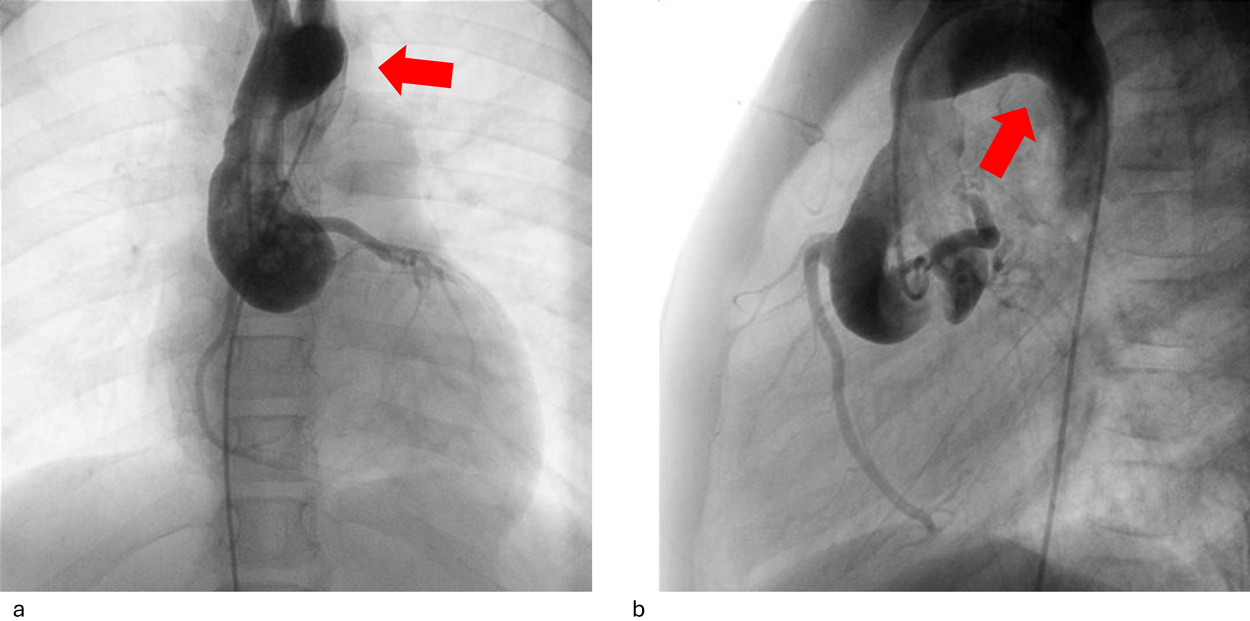

Impella®循環補助用心内留置型ポンプカテーテル(Impella® CP)と静動脈型体外式膜型人工肺により劇症型心筋炎の左室unloadingが著効した12歳男子例—体格の小さい患者における管理上の注意点A 12-year-old male case of successful left ventricular unloading utilizing Impella CP® and veno-arterial extracorporeal membrane oxygenation due to fulminant myocarditis—Precautions for management in patients with small stature